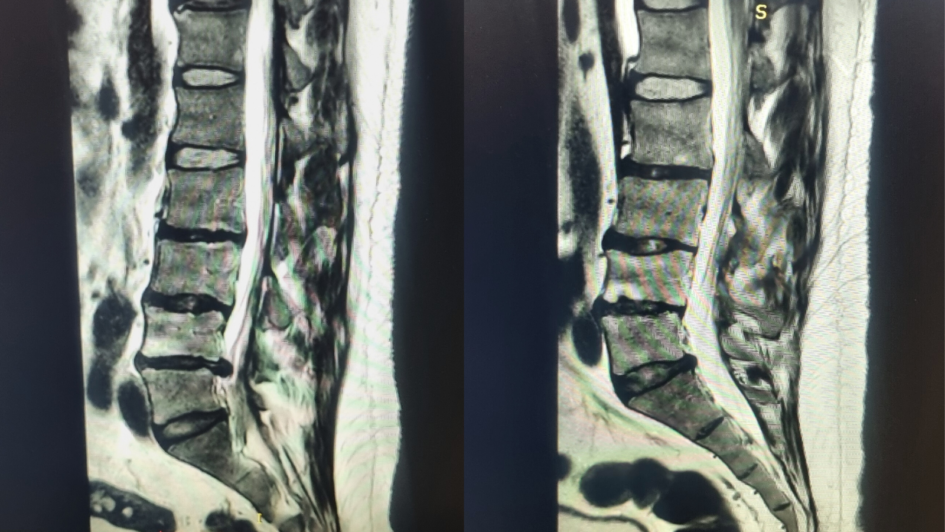

Podczas pierwszej konsultacji pacjent zgłaszał dolegliwości bólowe w okolicy biodra lewego z promieniowaniem do kończyny dolnej, które nasiliły się po pracy fizycznej z dźwiganiem ciężarów. W obrazie rezonansu magnetycznego stwierdzono dyskopatię nawrotową na poziomie L4/L5 oraz zmiany zwyrodnieniowe w obrębie kręgosłupa lędźwiowego. Mimo wcześniejszego zabiegu operacyjnego pacjent nie podjął jeszcze rehabilitacji, a leczenie ograniczało się do doraźnego stosowania środków przeciwbólowych. Doktor po zapoznaniu się z aktualnym rezonansem zalecił rozpoczęcie fizjoterapii.

Podczas kolejnej konsultacji, uzupełnionej o aktualny rezonans magnetyczny, stwierdzono znaczną poprawę. Badanie obrazowe nie wykazało cech dyskopatii nawrotowej ani zwężenia kanału kręgowego. Pacjent przestał korzystać z leków przeciwbólowych,, a wcześniej zgłaszane dolegliwości ustąpiły. Lekarz podkreślił znaczenie rehabilitacji i zalecił kontynuację ćwiczeń stabilizacyjnych oraz utrzymanie zdrowego trybu życia z unikaniem przeciążeń.